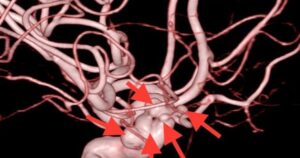

Tắt kịp 5 “quả bom” ẩn trong đầu người phụ nữ

Bệnh viện Đa khoa quốc tế S.I.S Cần Thơ (Bệnh viện S.I.S Cần Thơ) tối 26-10 cho hay vừa can thiệp kịp thời cứu một phụ nữ thoát đột quỵ do 5 túi phình mạch máu não chèn ép. Bệnh nhân là bà L.M.G.T (62[...]